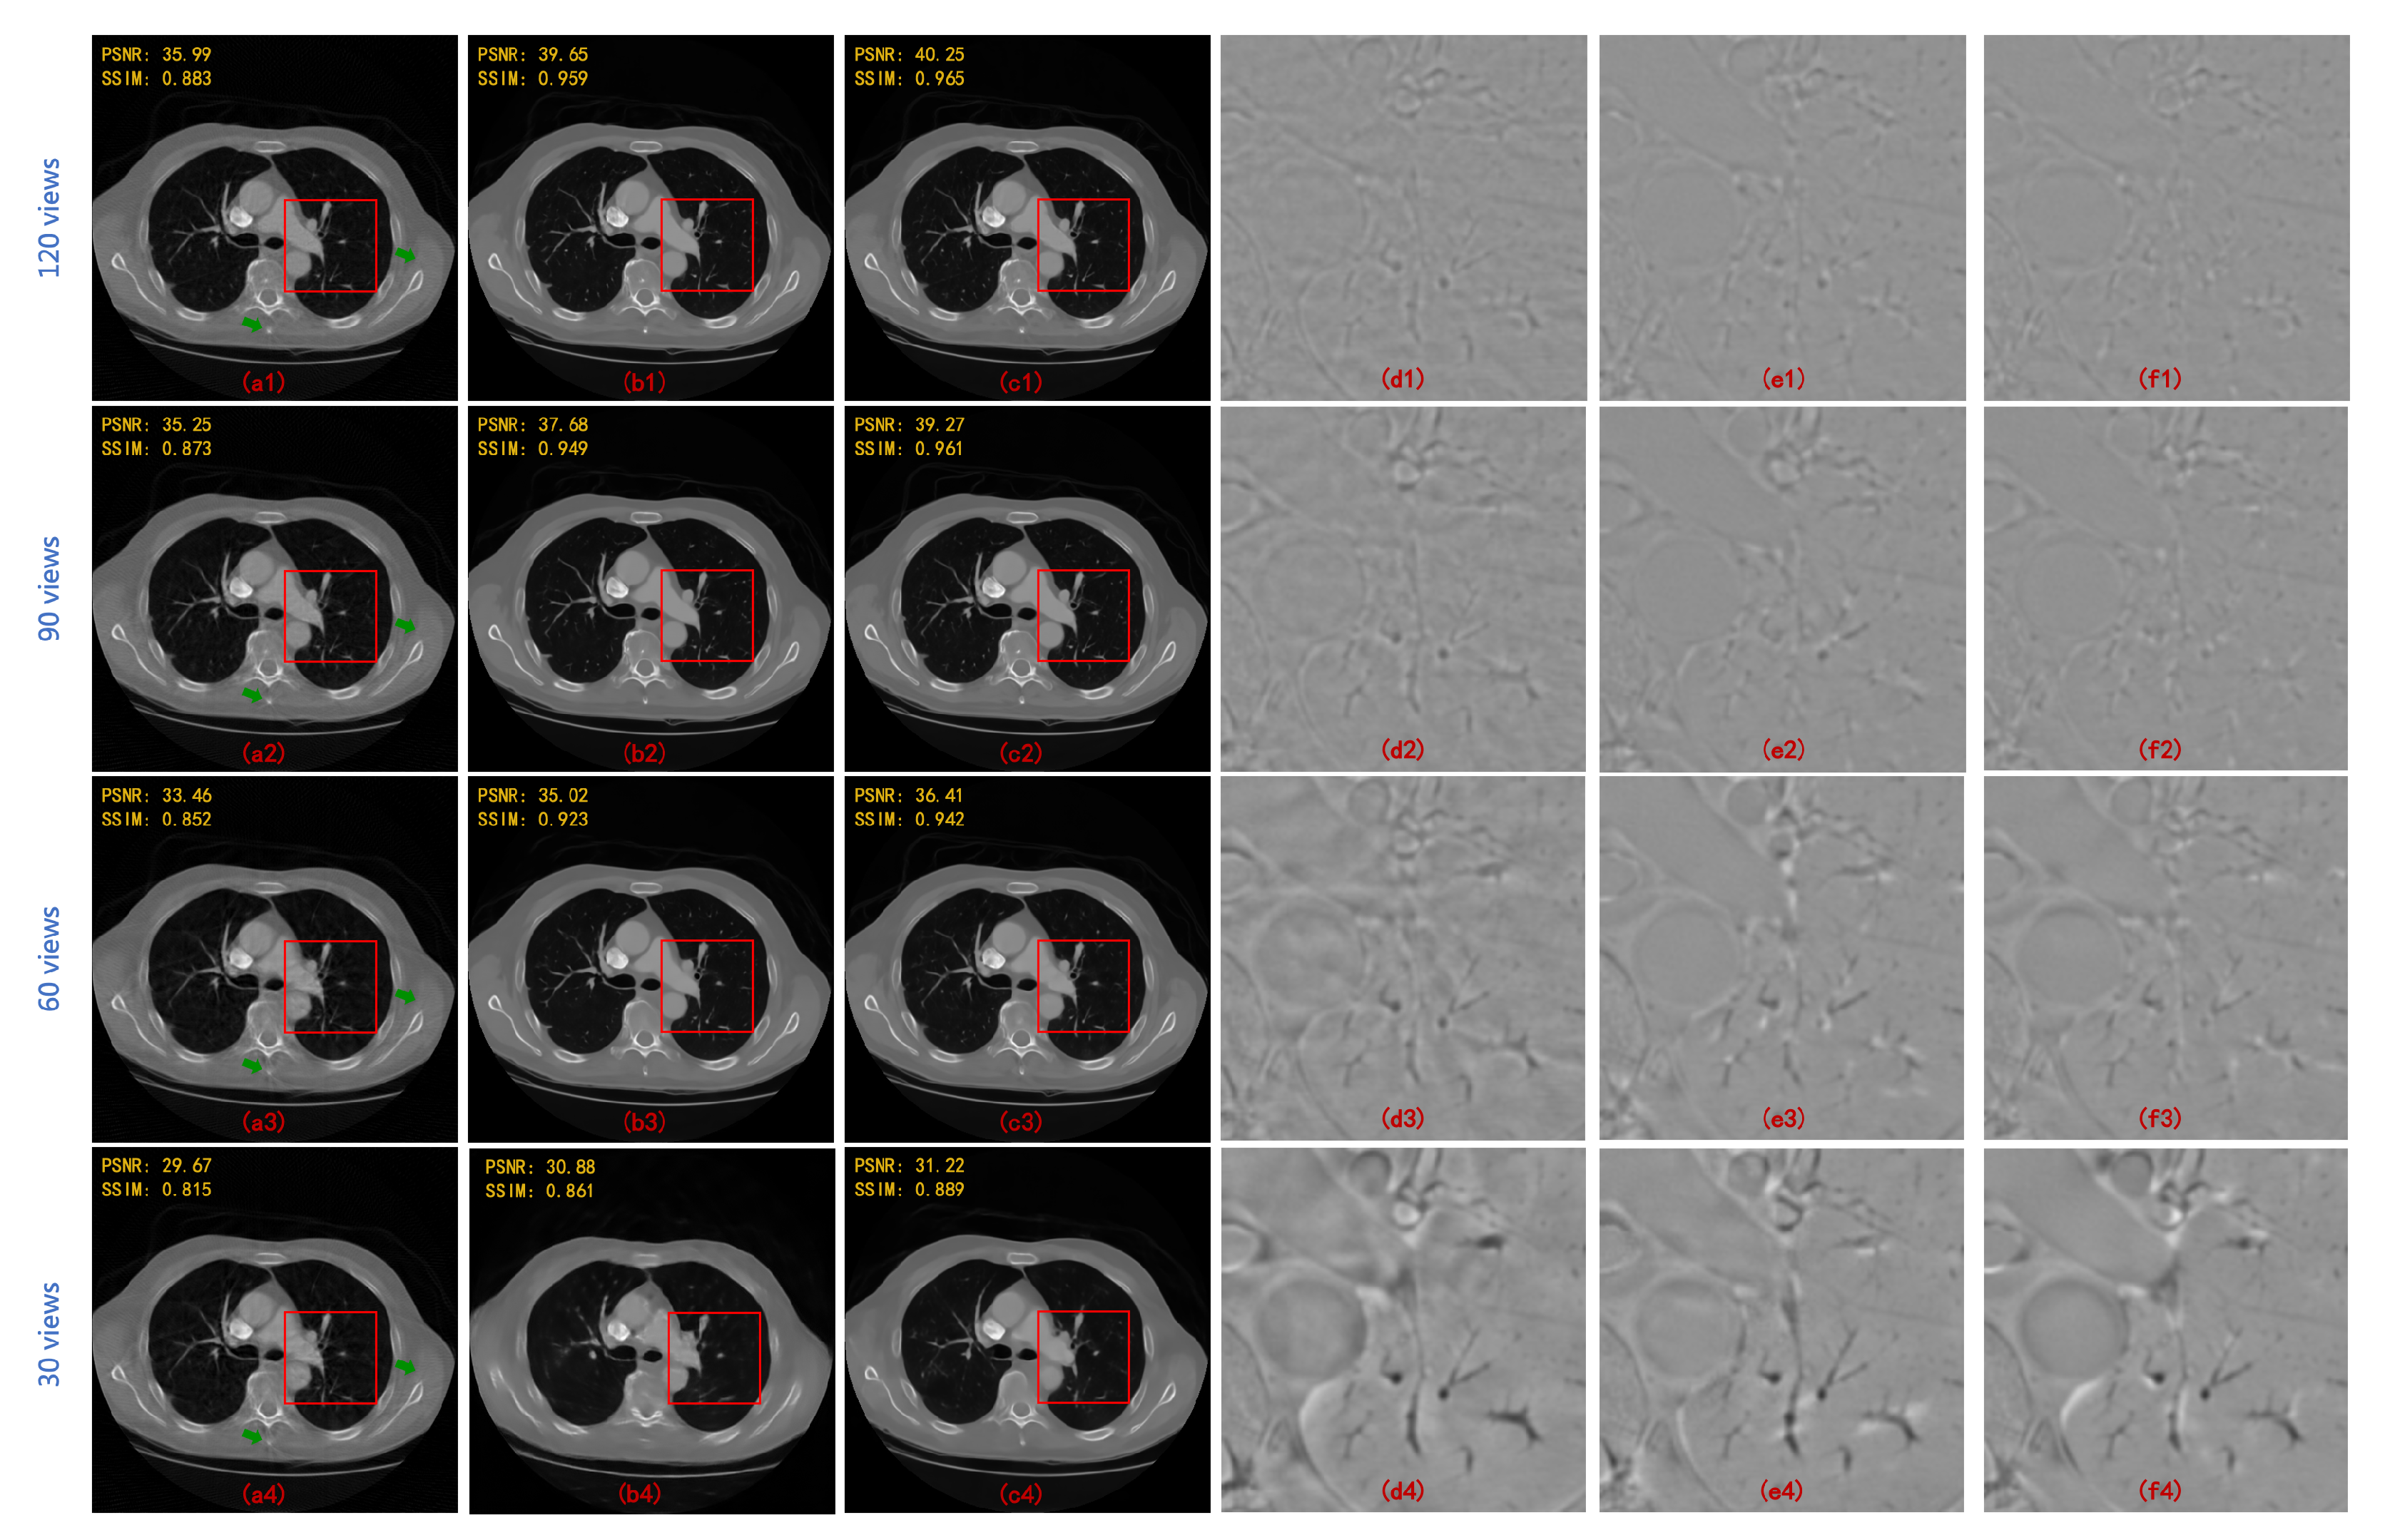

| 90 Views | 60 Views | |||

|---|---|---|---|---|

| PSNR | SSIM | PSNR | SSIM | |

| FBPConvNet [13] | 37.611 | 0.921 | 35.578 | 0.896 |

| RED-CNN [14] | 37.209 | 0.902 | 34.528 | 0.859 |

| DD-Net [22] | 36.380 | 0.912 | 34.424 | 0.892 |

| MWCNN [23] | 38.664 | 0.943 | 36.531 | 0.921 |

| HDNet (WCNN-based) [29] | 34.506 | 0.900 | 32.259 | 0.869 |

| HDNet (Unet-based) [30] | 35.459 | 0.903 | 33.377 | 0.886 |

| HDNet (WUnet-based) | 36.750 | 0.924 | 35.132 | 0.904 |

| HDNet (MWCNN-based) | 40.204 | 0.956 | 37.718 | 0.938 |